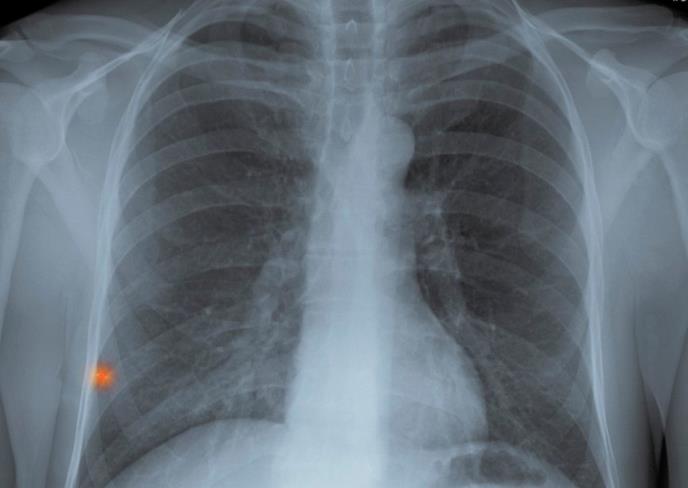

Devojčica je primljena u bolnicu sa glavoboljom, slabošču i problemima sa disanjem. Umrla je ubrzo po prijemu, a dr Aleksandar Fasl iz inzbruške bolnice kaže da je reč o milijarnoj tuberkulozi, veoma retkom i teškom obliku ove bolesti.

"Zbog atipičnih simptoma kao što su glavobolja i slabost, bolest se teško otkriva. Važno je smiriti javnost i reći da je prvih 20 nalaza u redu, a da se na ostale čeka nekoliko nedelja", kaže dr Fasl.